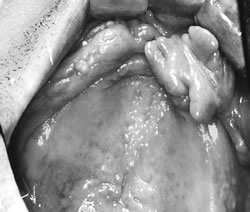

歯科のかかわりで、しっかり噛めるようになりアルブミン値も改善。線維腫を摘出、義歯製作

写真

術前

術後

対象患者さんは自分の歯で充分な咀嚼ができる人は約1割のみで、残りの約9割が充分な咀嚼をするには義歯が必要な人です。その約半数は、義歯使用上の問題を抱え、うまく噛めない人でした。 60 代の男性は上下無歯顎で、上顎義歯が不安定で外れやすく、咀嚼障害がありました。上顎歯肉部には、これまでの不適合義歯により「ビラビラした歯ぐき(線維腫)」ができていました。この浮動性の歯肉が、義歯の安定性と吸着力を阻害した原因でした。歯科では、不適合義歯を調整し、線維腫の摘出と歯肉の形態修正手術を行いました。その後、新しい義歯を製作しました。その結果、食事介助も円滑になり、摂取量も増えました(写真)。